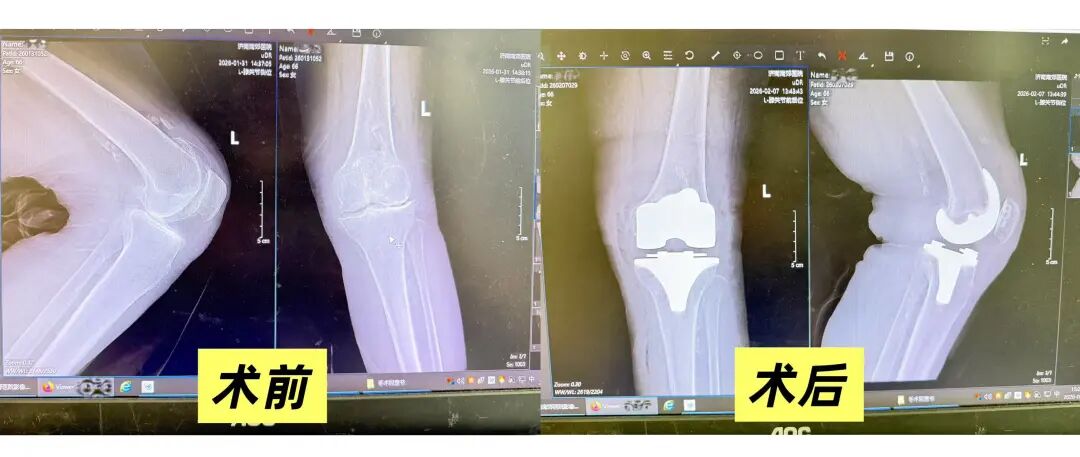

骨二科杨学良主任带领团队对患者病情进行了全面评估。患者病程长达十年,保守治疗未能阻止病情进展,近期症状显著加重,左膝受累更重,已明显影响生活质量。结合临床表现与影像学资料,团队判断其双侧膝关节骨性关节病已进入中晚期,左膝软骨磨损、骨质增生及关节间隙狭窄等病理改变突出,保守疗法难以根本改善。

为确保手术安全与疗效,杨主任骨科团队完善了双膝X线及MRI等影像学检查,明确关节内软骨、半月板、韧带及骨赘的具体情况,并行血常规、凝血功能、肝肾功能等术前评估,排除手术禁忌。在与患者及家属充分沟通病情、手术方案及预期效果后,杨学良主任团队为其施行左侧膝关节置换术,以人工关节替代受损关节面,旨在解除疼痛、恢复关节功能、显著提高生活质量。